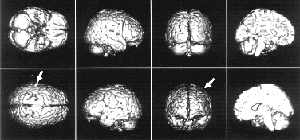

В развитых странах, прежде всего в США, клинический стереотаксис занял достойное место в нейрохирургии. В США в этой сфере сегодня работают около 300 нейрохирургов — членов Американского стереотаксического общества. Основа стереотаксиса — математика и точные приборы, обеспечивающие прицельное погружение в мозг тонких инструментов. Они позволяют „заглянуть“ в мозг живого человека. При этом используется позитронно-эмиссионная томография, магниторезонансная томография, компьютерная рентгеновская томография. „Стереотаксис — мерило методической зрелости нейрохирургии“ — мнение ныне покойного нейрохирурга Л.В. Абракова. Для стереотаксического метода лечения очень важно знание роли отдельных „точек“ в мозге человека, понимание их взаимодействия, знание того, где и что именно нужно изменить в мозге для лечения той или иной болезни.

Существуют два вида стереотаксиса. Первый, нефункциональный, применяется тогда, когда в глубине мозга имеется какое-то органическое поражение, например опухоль. Если её удалять с помощью обычной техники, придётся затронуть здоровые, выполняющие важные функции структуры мозга и больному случайно может быть нанесён вред, иногда даже несовместимый с жизнью. Предположим, что опухоль хорошо видна с помощью магниторезонансного и позитронно-эмиссионного томографов. Тогда можно рассчитать её координаты и ввести с помощью малотравматичного тонкого щупа радиоактивные вещества, которые выжгут опухоль и за короткое время распадутся. Повреждения при проходе сквозь мозговую ткань минимальны, а опухоль будет уничтожена. Мы провели уже несколько таких операций, бывшие пациенты живут до сих пор, хотя при традиционных методах лечения у них не было никакой надежды.

Суть этого метода в том, что мы устраняем „дефект“, который чётко видим. Главная задача — решить, как до него добраться, какой путь выбрать, чтобы не задеть важные зоны, какой метод устранения „дефекта“ выбрать.